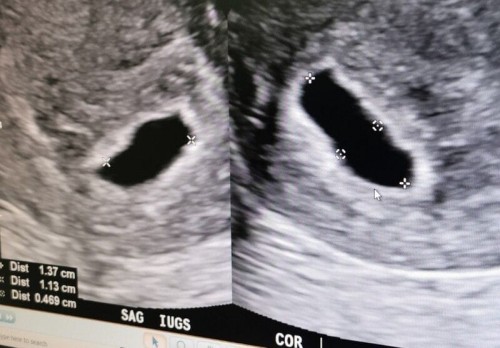

Week 5 day 5

Rushed to Kk's hospital after spotting for 2 days without cramping / pain, spent 6 hours there for all the investigations. Grateful that there is no miscarriage and no ectopic pregnancy. Based on my calculations from last menstrual date, I thought I should be at week 8.. But from the ultrasound, baby is just week 5 day 5, can only see gestational sac but cant see baby.. Anyone can't see baby too in week 5? #firstbaby #pregnancy #1stimemom #advicepls #ultrasound